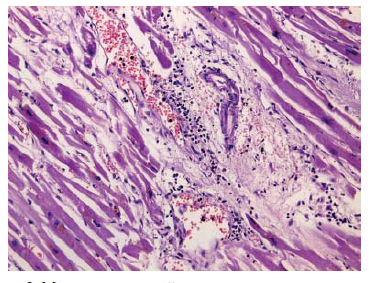

Результаты и их обсуждение. В зависимости от степени выраженности деструктивно-воспалительных поражений тканей органов все наблюдения были распределены следующим образом [10]: 1 – макроскопически различимые абсцессы (6 чел.); 2 – микроскопические абсцессы (4 чел.) (рис. 1); 3 – с минимально выраженным гнойным метастазированием в виде мини-очажков, представляющих собой скопления до 10 лейкоцитов, часть из которых – нейтрофильные гранулоциты (22 чел.) (рис. 2); 4 – без признаков гнойного метастазирования (13 чел.).

Рис. 2. Метастатический мини-очажок в миокарде, окраска гематоксилином и эозином, ув. ×200